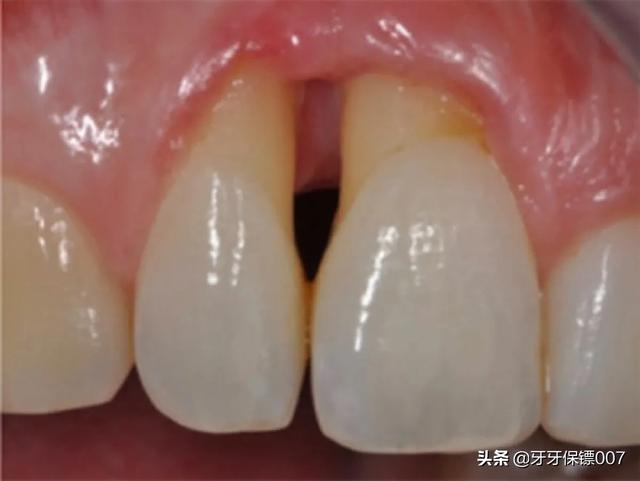

• 牙齿松动

牙齿松动,这是很多牙周炎患者就诊的主要原因。松动是因为牙槽骨发生吸收,牙齿失去扶持作用而松动。